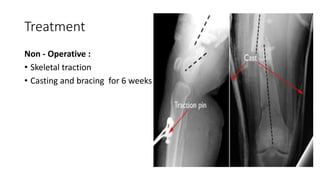

Non - Operative :

• Skeletal traction

• Casting and bracing for 6 weeks